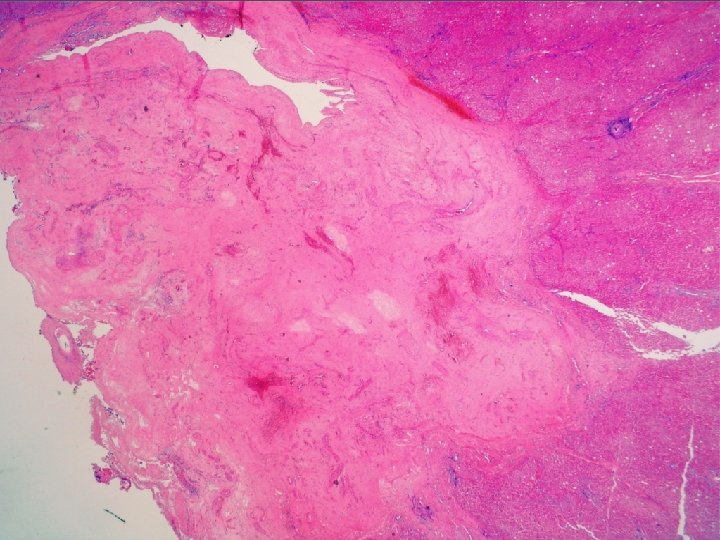

Naša diagnóza Segmentálna atrofia pečene, stage II / nodulárna elastóza pečene

Segmentálna atrofia pečene • zriedkavý pseudotumor • častejšie u žien, unifokálny • najčastejší príznak bolesť horného pravého kvadrantu • prevažne subkapsulárne • 1, 8 - 10 cm • abnormálne hrubostenné cievy (len intralezionálne), často trombotizované, rekanalizované • biliárne cysty

Elastika? • v poškodených tkanivách sa môže tvoriť nadmerné množstvo (dezorganizovaných) elastických vlákien • v pečeni normálne v stenách ciev, malé množstvo v portálnych poliach a okolo centrálnej vény • pri poškodení produkujú portálne fbroblasty • prečo tak exuberantne?

Abnormálne cievy • vyvolávajúci impulz ischémia?